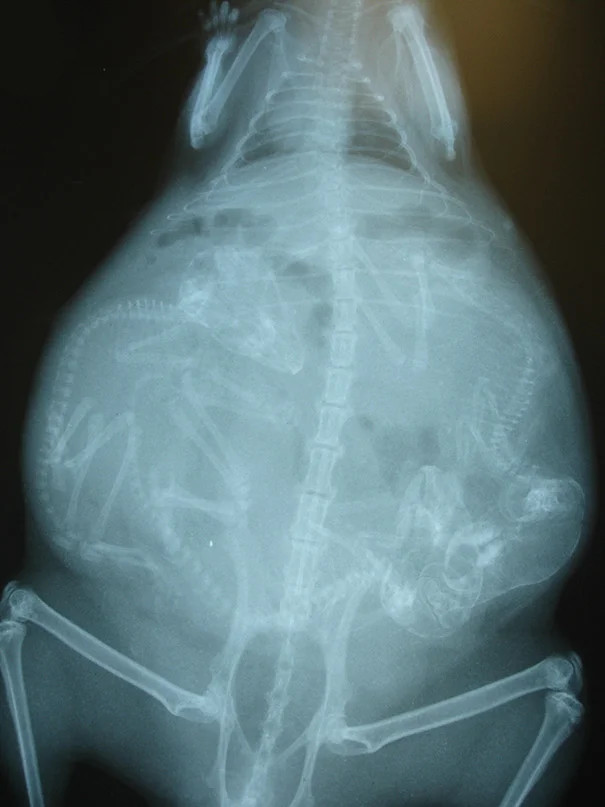

Poruchy při porodu

U činčil se nejčastěji vyskytují různé problémy při porodu.

Symptomy: Březí činčila ve vysokém stupni březosti je apatická, nekomunikativní, nebere si potravu, sedí neustále na jednom místě, snaží se vyvolat porod tlačením. Sedí sklesle a nebo leží na boku.

Možné příčiny: Příčinou mohou být příliš velké plody, plody nacházející se pouze na jedné straně v děloze samičky, nekróza v těle samičky, letální faktor, porody po 3 měsících - tedy ihned po sobě, nebo připuštění samičky v moc mladém věku. Pokud se plody vyskytují pouze na jedné straně, nebo jsou příliš velké, samice není schopna mláďata porodit.

Léčba: Chybné polohy plodů, nebo velké plody Ize diagnostikovat rentgenologicky. Pokud přetrvává apatie u samice a stále se nerodí mláďata, je nutné ihned vyhledat veterináře specializovaného na porody drobných savců. Veterinář provede císařský řez. S tímto je ovšem spojena i kastrace samice. Pokud je v těle činčily nekróza, je potřeba ihned nekrotickou část vyoperovat. Často ovšem pro samičky bývá pozdě, jelikož se často nekróza utvoří ještě před porodem. Letální faktor je faktor kdy mládě není schopno života díky nefunkčním některým funkcím důležitým k životu. Tento faktor se nalézá v genech bílých činčil a v genech činčil se znaky velveta. U každé této mutace se ale vyskytují na jiném lokusu a proto se mohou křížit bílé činčily s velvety, ale ne bílá x bílá či velvet x velvet. U bílých činčil se nejčastěji stane, že mládě zemře ihned po porodu nebo ještě v těle matky a ta jej buďto porodí mrtvé nebo vlivem nekrózy tělíčka v těle matky zmírá i matka. U velvetů samice často plody potrácejí, tedy narodí se předčasně mrtvé. Toto se může dít i u neletálních činčil právě vlivem ostatních příčin.

zde porozená siamská dvojčata přirostlá bříšky, která matka nemohla vytlačit kvůli velikosti plodu. Mláďata nepřežila.

Snímek se 3 mláďaty

zdroj: Buyxraysonline